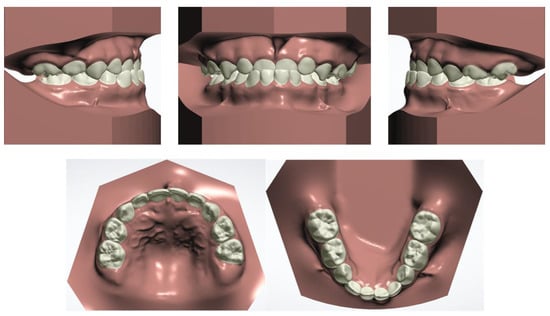

The clinical examination revealed a convex profile with protrusion of the upper and lower lips and hypertonia of the lip muscles (Figure 1). An intraoral examination identified a primary dentition phase. Centric occlusion examination indicated a Class III terminal molar relationship with a bilateral posterior scissor bite. The left posterior teeth presented a complete scissor bite with no contact on the occlusal surface, which was worse than their right counterparts (Figure 2 and Figure 3). An anterior crossbite was observed with a reverse overjet and overbite. Furthermore, the jaw could be retracted to display an edge-to-edge bite when guided backward. The mandibular incisors were upright, with the upper incisors slightly lingually inclined. The upper and lower dental midlines were aligned with the facial midline. No functional mandibular shift was observed when the mouth was open, and no clicking or pain was detected in the TMJ area. Moreover, habitual mandibular protraction at rest and during speech was observed.

The patient and his parents allowed the use of his medical records, photographs and radiographs in this research. Prior to the initiation of therapy, panoramic and lateral cephalometric films were obtained. The panoramic radiograph showed swelling in the bilateral nasal mucosa (Figure 4). A mild skeletal Class II sagittal relationship (ANB = 5.4°) and large mandibular plane angle (SN-MP = 39.8°) were indicated in the pre-treatment cephalometric film (Table 1). Meanwhile, his hyoid (MP-H) rested lower than normal (16.8 mm, mean normal = 14.2). In addition, he had a hyperdivergent growth pattern (facial height index, S-Go/N-Me = 57.9%). The airway width assessment showed that he had a limited nasopharyngeal airway gap and expanded oropharyngeal segments (data shown in Table 1). His adenoids were diagnosed with moderate hypertrophy (Figure 5) with an A/N of 64.5% [11,12], which was derived from an adenoidal–nasopharyngeal ratio (AN ratio) via linear measurements using lateral radiographs of the nasopharynx according to Fujioka et al. and Zou. et al. [11,12]. Considering that adenoids in children are physiologically enlarged between 2 and 12 years of age, Zou proposed that an A/N ratio of 0.60 should be considered as normal; 0.61–0.70 is considered as moderate hypertrophy; ≥0.71 is considered as pathological hypertrophy [12]. The digital models’ STL files were uploaded to the Geomagic Studio 12.0 software (Research Triangle Park, NC, USA) for measurement (Figure 6 and Figure 7). The statistics concerning the widths of the dental arch and basal skeletal, as well as the height, surface area and volume of the palatal, are displayed in Table 2.

Figure 2. Initial digital study models.

Jcm 12 00333 g002